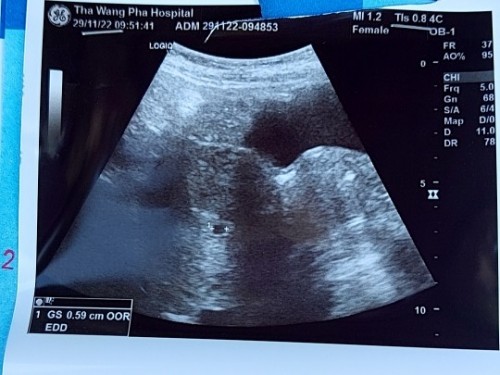

ท้อง9weekไม่พบตัวอ่อน

เราท้องได้9weekแต่ไปซาวกับไม่เจอตัวน้องคะซาวทั้งหน้าท้องและทางช่องคลอดตอนนี้เครียดมากการคัดเต้าก็ยังปกติคะมีเหม็นกลิ่นอาหารบ้างตอนนี้จิตตกเข้าออกตามเว็บหาข้อมูลทำใจไม่ได้เลยคะแม่ท่านไหนเป็นแบบนี้บ้างคะ